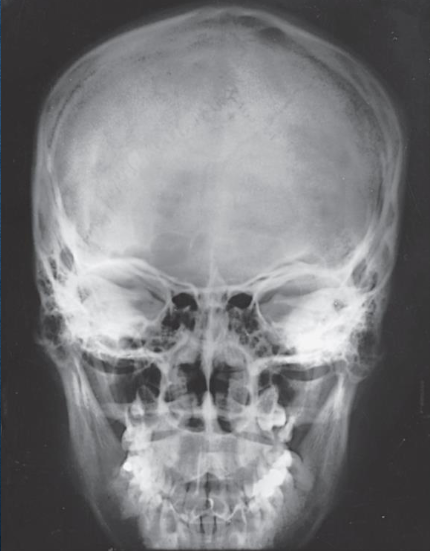

PA skull image criteria

evidence of proper collimation

entire cranial perimeter showing three tables of squamous bone

no rotation:

equal distance from lateral borders of skull to lateral border of orbits

symmetric petrous ridges

petrous ridges fill orbits

penetration of frontal bone without excessive density of lateral borders of skull

PA axial (Caldwell) skull image criteria

petrous ridges demonstrated in lower third of orbits

AP/AP axial (Reverse Caldwell) skull image criteria

shows the same as PA and PA axial projections

evidence of proper collimation

entire cranial perimeter showing three tables of squamous bone

no rotation:

equal distance from lateral borders of skull to lateral border of orbits

symmetric petrous ridges

anatomy is more magnified